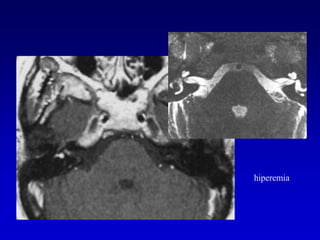

El realce lineal fusiforme con Gd al interior del CAI puede ser ocasionado por:Pequeño Schwannoma (T2  muestran un nódulo sobre el nervio)Neuritis (T2  grosor del nervio normal)AICA normal (T2  pueden confirmar)Invasión  meníngea o hiperemia (T1 con matriz de 512 x 512  Gd pueden distinguir realce a lo largo de las paredes del CAI en vez del centro del CAI)

hiperemia